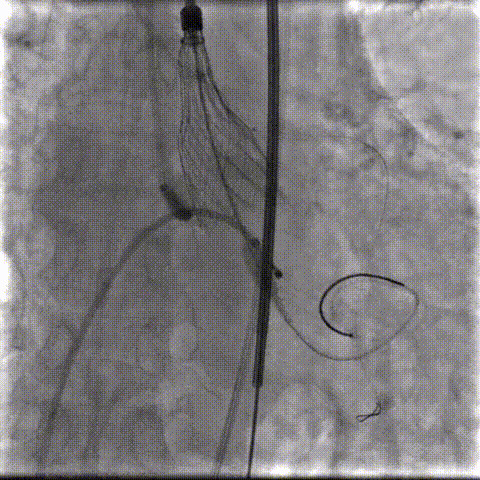

瓣环下精准定位稳定释放,瓣膜工作位造影考虑瓣叶推挤LCA阻挡临界状态,释放“烟囱支架”。

瓣膜稳定脱钩,20mm球囊后扩,“烟囱支架”Kissing,后扩后支架形态改善。